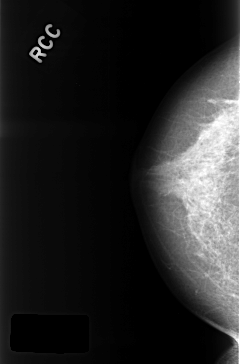

C_0320_1.RIGHT_CC

RIGHT_CC LINES 4360 PIXELS_PER_LINE 2872 BITS_PER_PIXEL 12 RESOLUTION 50 NON_OVERLAY